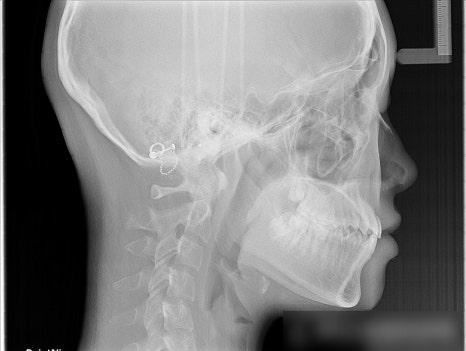

환자분의 악골관계(위아래 턱뼈)를

살펴볼 수 있는 방사선 사진에서

그 원인을 발견할 수 있었습니다.

아래턱이 한쪽으로 틀어진

골격적 비대칭 문제였습니다.